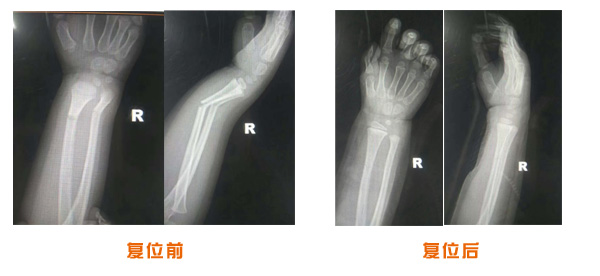

肥城市安駕莊梁氏骨科醫(yī)院是一所以梁氏手法正骨配合膏藥為特色的現(xiàn)代化??漆t(yī)院。

梁氏骨科術(shù)始創(chuàng)于清雍正年間,歷經(jīng)八代,至今已有三百年歷史。據(jù)1929年泰安縣志載“梁瑞圖先生,字增生,號(hào)蓮峰,安駕莊人,精岐黃并發(fā)明接骨,凡跌打車凡跌打車軋皮不破而碎骨者......【詳細(xì)】 |